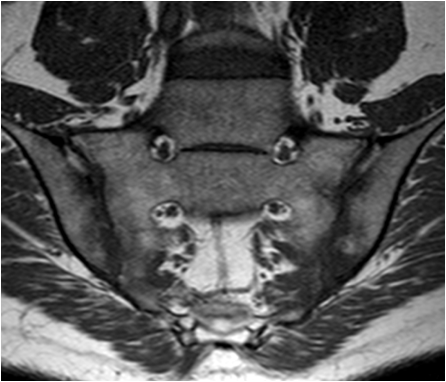

Inflammatory synovial changes and subchondral edema are well seen on MRI. MRI is more sensitive and is being used with increased frequency to detect and stage inflammatory nvolvement of the sacroiliac joint in patients with ankylosing spondylitis.

Fig. 16. T1 weighted and STIR images of the sacroiliac joints in a young patient with low back pain. Low signal areas on T1 correspond with edema seen on STIR. Note the joint space narrowing and the more pronounced subchondral changes in the iliac bone as compared to the sacrum.